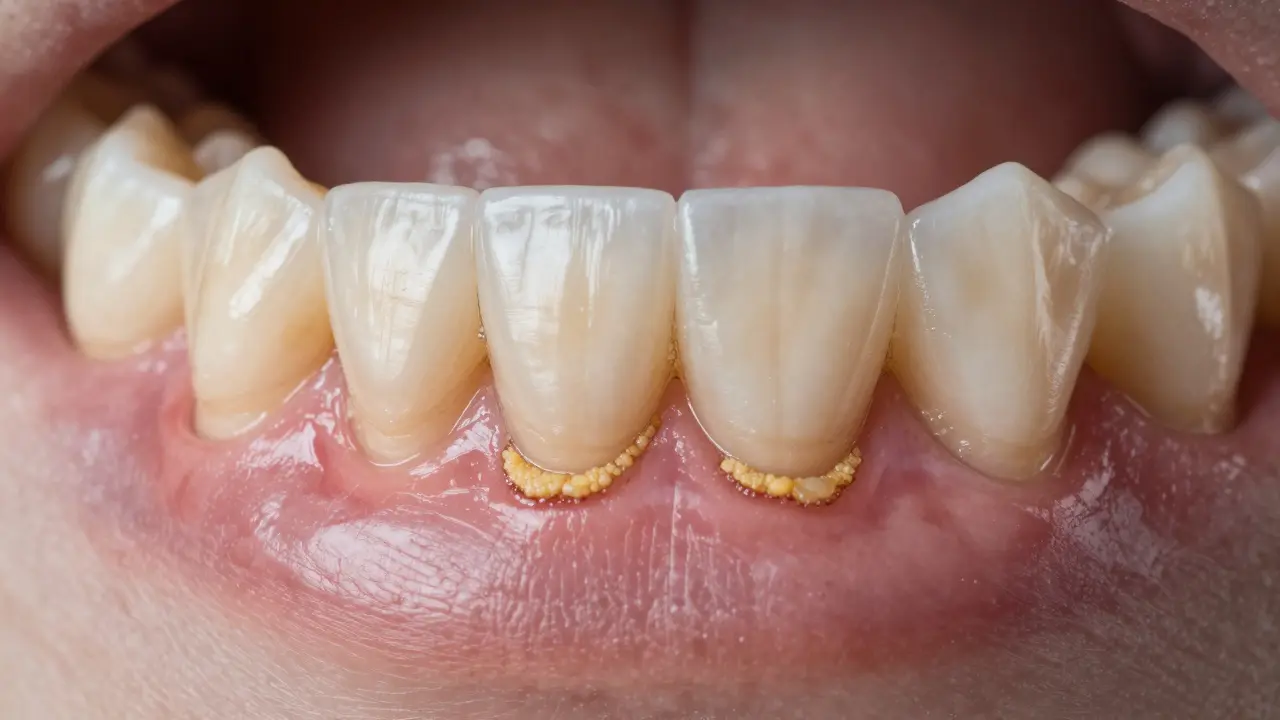

Tento počáteční kámen je často jen tenká, půl milimetru tlustá vrstvička, která se tvoří především u spodních řezáků a u zubů, které se dotýkají slinných žláz. Vypadá jako lehce žlutý nebo šedivý pruh, který se nechce odstranit i po důkladném čištění. Většina lidí ho přehlíží - myslí si, že to je jen „špína“, kterou si zvykli.

Když se kámen začne tvořit, nezůstává jen na povrchu. Bakterie v něm produkují kyseliny, které poškozují sklovinu zubu. Zároveň dráždí dásně. První příznaky? Červené, krvácivé dásně při čištění, zápach z úst, který nezmizí ani po vypláchnutí. To není jen „zápach z jídla“ - je to zánět dásní, tzv. gingivitida.